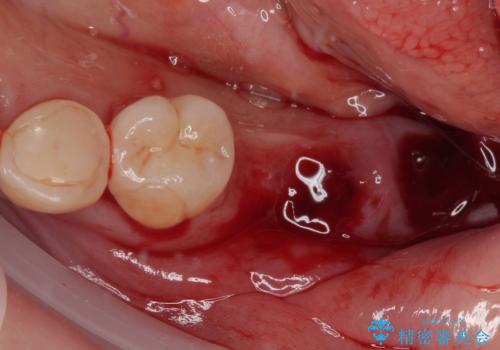

上顎は最後臼歯が欠損しているため、ブリッジの土台は抜歯し、元々の欠損部にインプラントによる補綴治療を行うこととしました。

支台歯の骨欠損は予想以上に大きく、即時荷重インプラント部への影響が心配されましたが、無事に最短期間で治療を終えることができました。